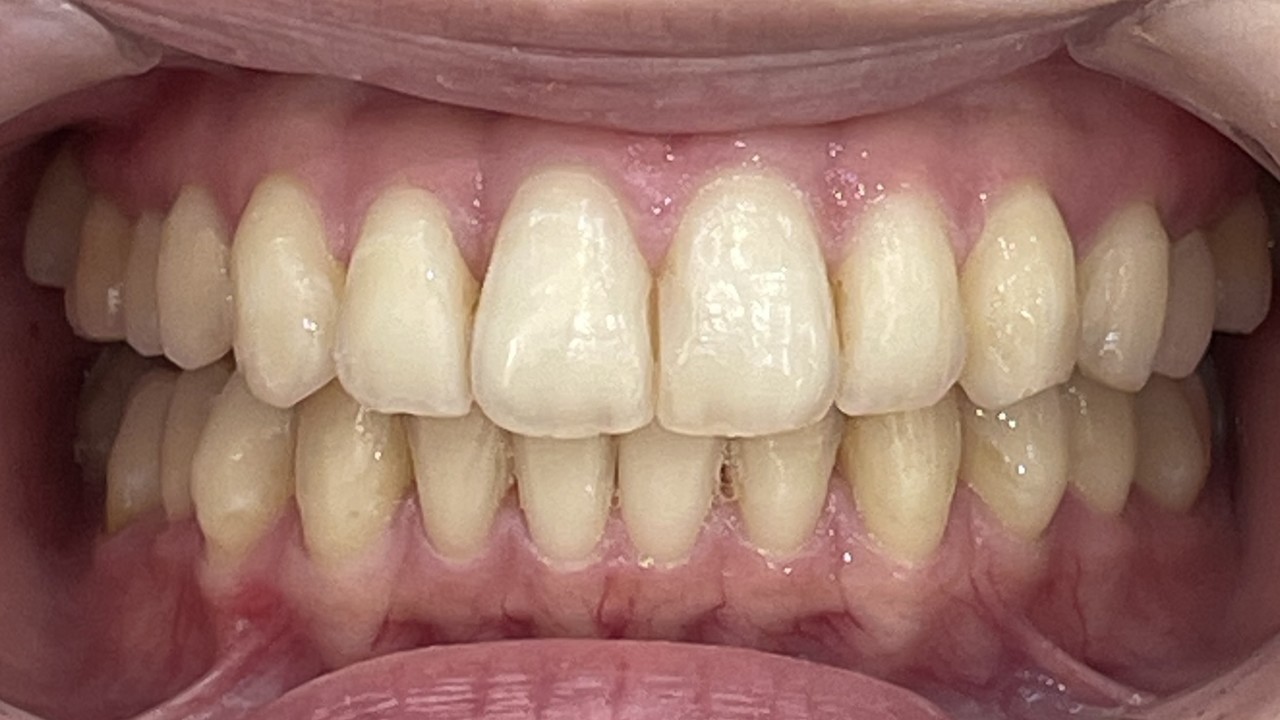

After

矯正の種類 / invisalign GO

年齢・性別 / 30代男性

主訴  /  上顎空隙

治療期間 / 18ヶ月

費用 / 簡易検査 5,000円(税別) 精密検査 30,000円(税別)

両顎マウスピース 450,000円(税別) 両顎リテイナー料 40,000円(税別)

※マウスピース交換時別途調節料5,000円(税別)

副作用 / 口内炎・歯の移動に伴う痛み・知覚過敏 ※数日で収まる場合が多いです

リスク / 後戻り防止の為、夜のみマウスピースで保定を指示